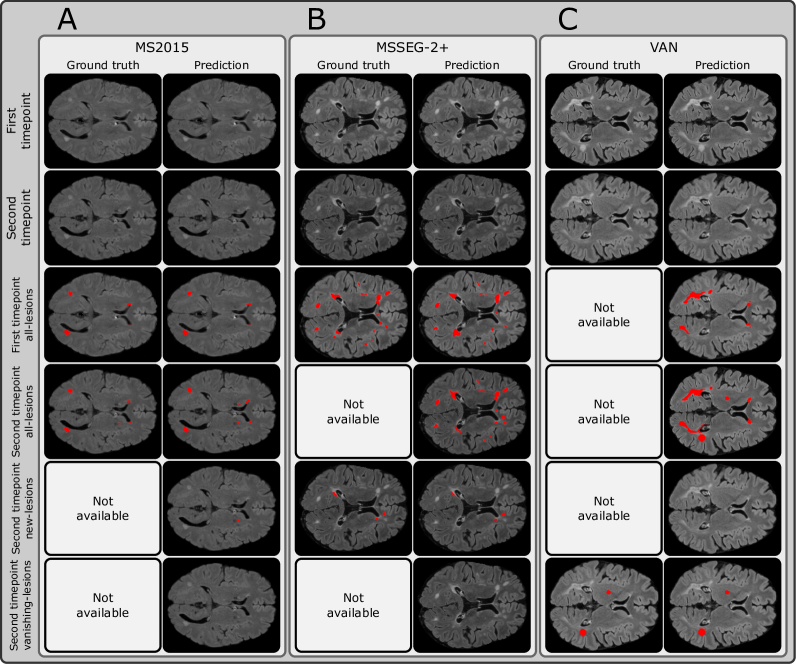

SegHeD is a unified model that can perform all-lesion, new-lesion, and vanishing-lesion segmentation tasks. We evaluate its multi-task performance and compare it against state-of-the-art (SOTA) task-specific segmentation methods, nnU-net [18], nnFormer [34], UNETR [15], a recent heterogeneous data learning method, CoactSeg [30], and specifically designed new-lesion segmentation methods [33, 1], shown in Table 2. Task-specific SOTA methods are trained twice, once for all-lesion segmentation task (using MS2015 and MS2016) and once for new-lesion segmentation task (using MSSEG-2). It is not possible to include the MSSEG-2+dataset into SOTA training, as these methods do not allow for the heterogeneous annotations which MSSEG-2+ possess. CoactSeg [30] is only trained once. For new lesion segmentation on MSSEG-2, we report Dice scores of MedICL [33], Basaran [1], and the average score of 4 human experts, Avg. of Experts, officially released by the challenge organisers [7], and include the lesion-wise scores in Table 3, in accordance with the MSSEG-2 challenge. Exemplar segmentations are compared in Figure 2, and further provided in Figure 3.

Table 2 shows that SegHeD significantly outperforms both task-specific SOTA methods and heterogeneous learning method CoactSeg in all-lesion segmentation task. For example, on MS2016 test set, SegHeD improves the Dice score by over 10%. This can be attributed to several factors. SegHeD allows heterogeneous data input and thus can include more images for model training (Table 5). The domain knowledge encoded via anatomical constraints also helps reduce false positives, as shown in Figure 2.